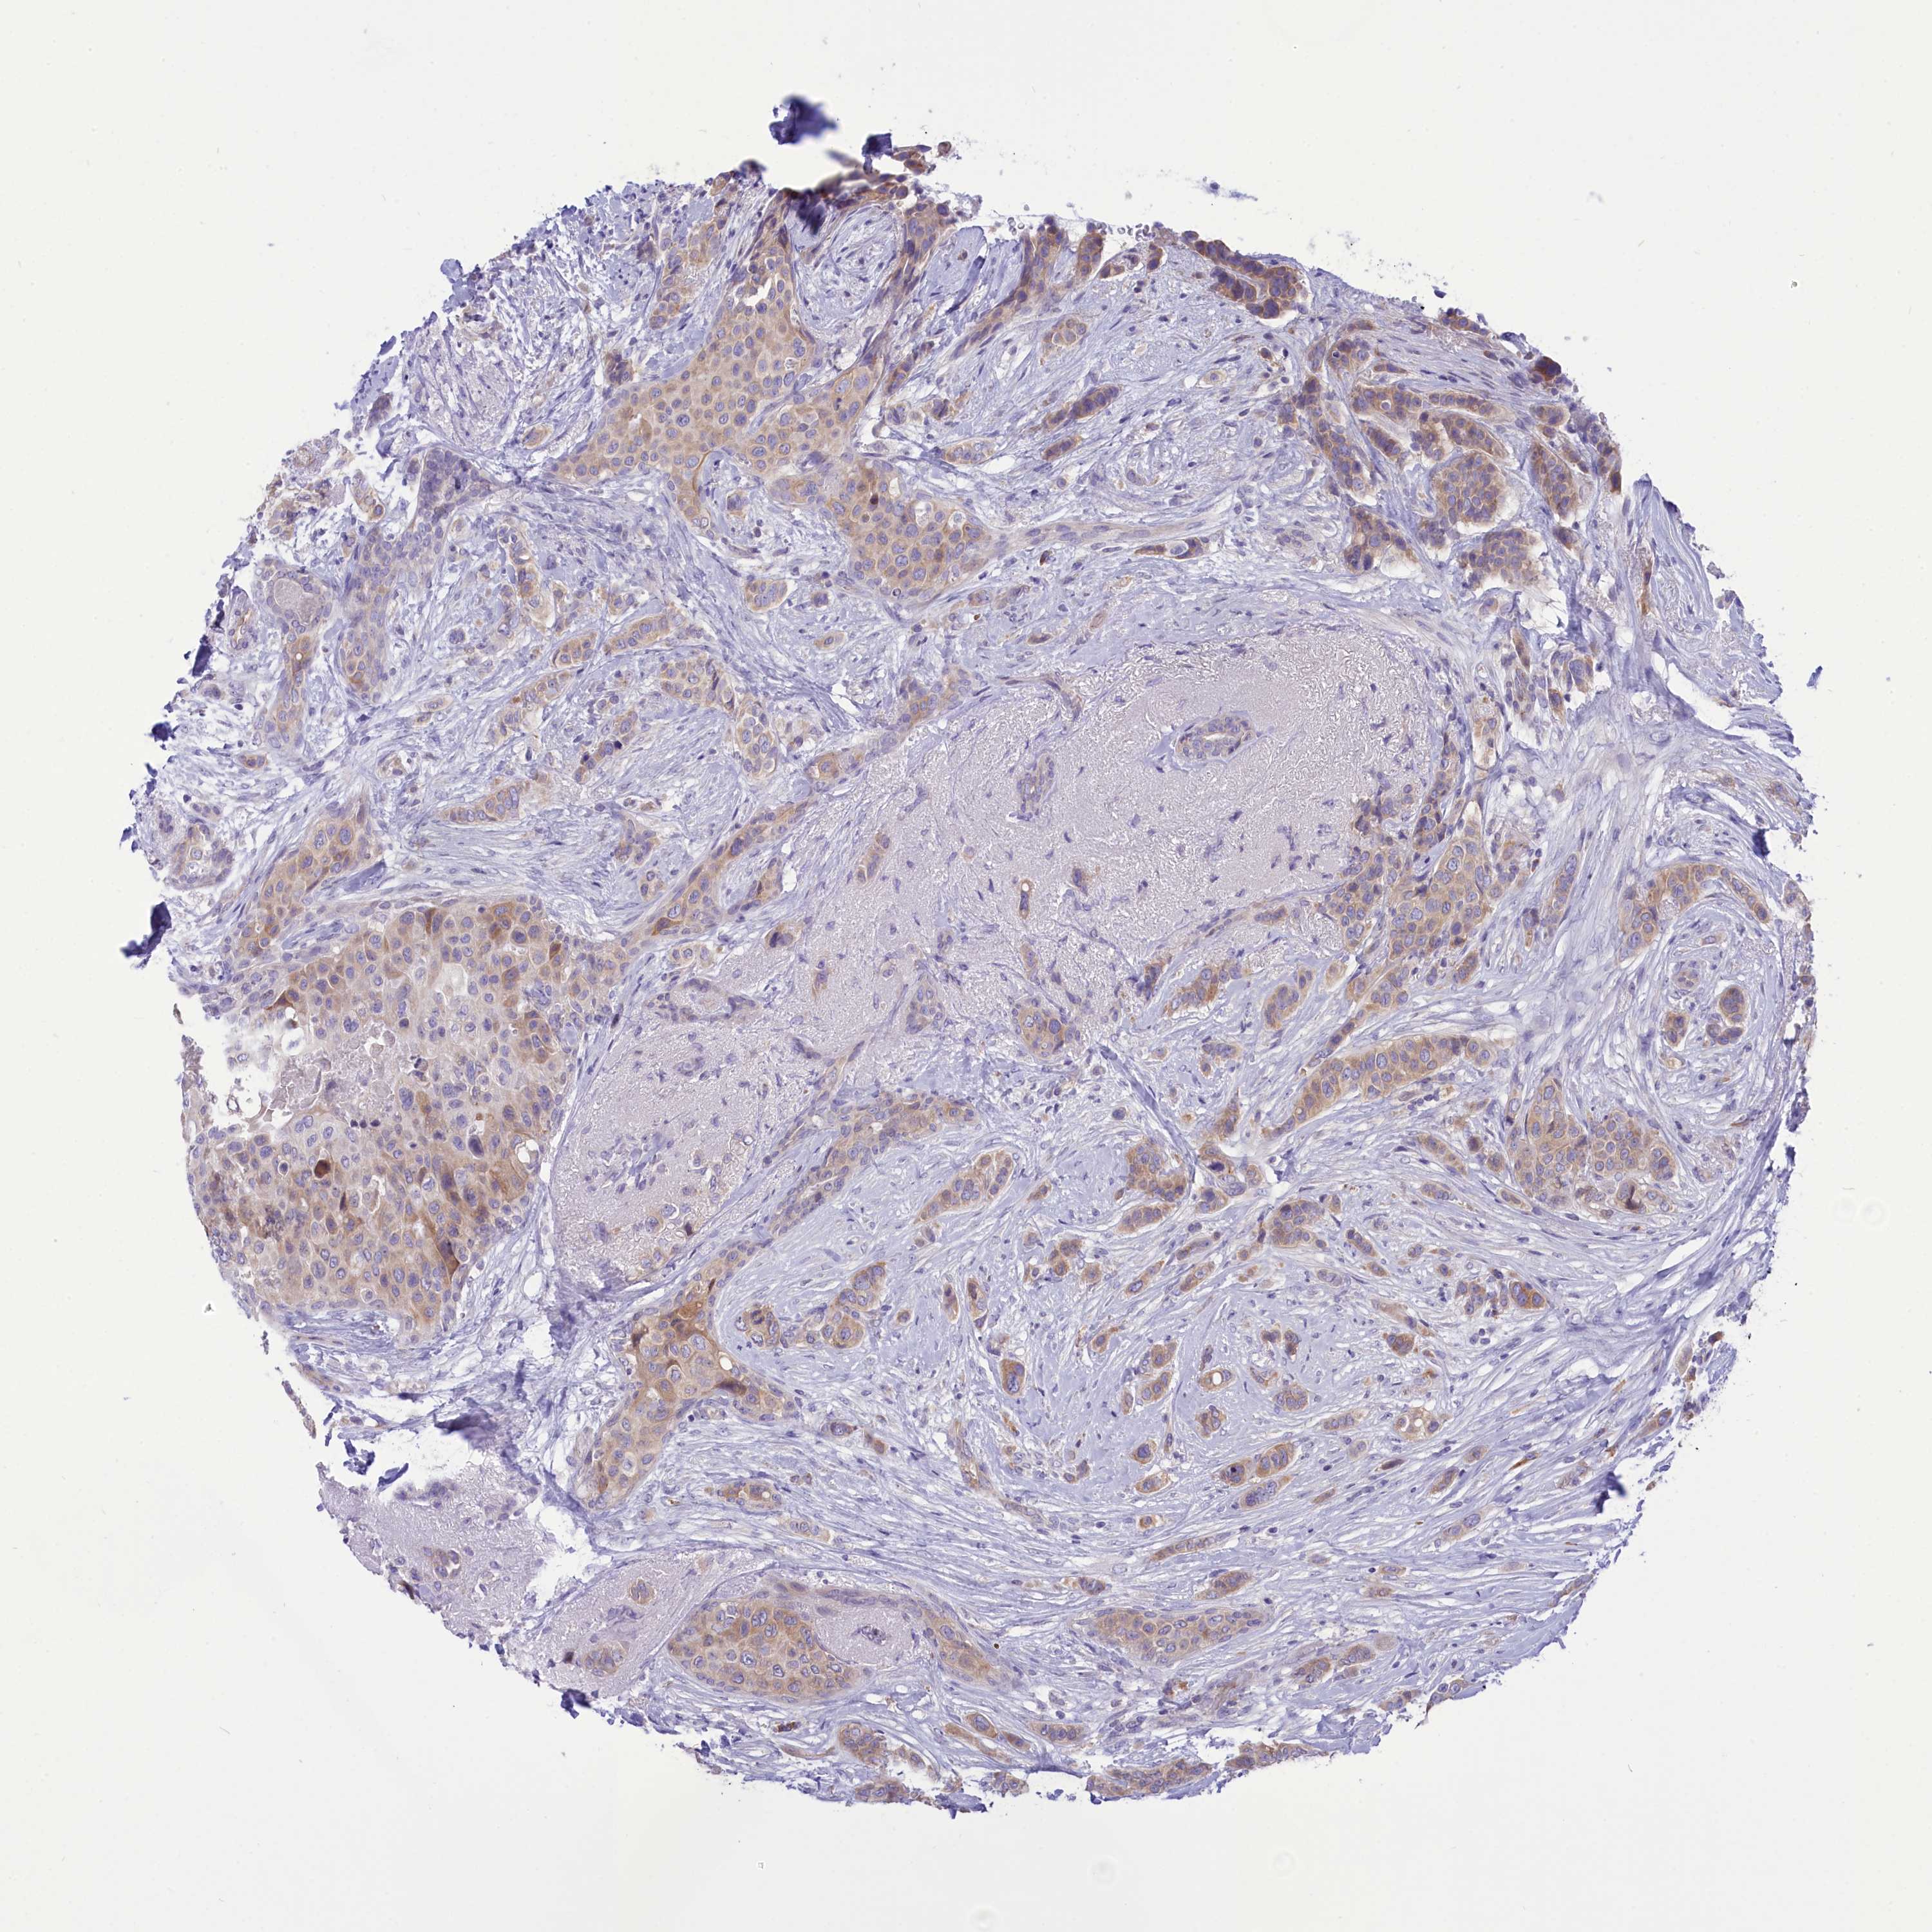

BRCA TCGA BRCA VALIDATION PROTEIN EXPRESSION

ANTIBODIES

AND

VALIDATION